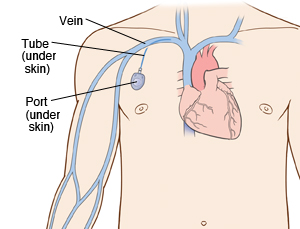

Overview

Package includes:

Days in hospital : 4 Days (For patient and one attendant)

Days in hotel : 10 Days (For patient and one attendant)

Room type in hospital : Shared

Room type in hotel : Private

Hotel category: Standard

Value added benefits of the Pacemaker Procedure Biventricular:

Ø Doctor consultation charges

Ø Lab tests and diagnostic charges

Ø Room charges inside hospital during the procedure

Ø Surgeon Fee

Ø Nursing charges

Ø Hospital surgery suite charges

Ø Anesthesia charges

Ø Routine medicines and routine consumables (bandages, dressings etc.)

Ø Food and Beverages inside hospital stay for patient and one attendant.

Extra benefits:

ü Interpreter

ü Visa assistance

Ø Site tourism of the city

Ø Follow up with the doctor

Ø Airport pick up and drop

Ø Free online consultation with the doctor

Ø Priority appointments with the doctor

Ø Room upgrade from sharing to private

Overview

Package includes:

Days in hospital : 3 to 4 Days (For patient and one attendant)

Days in hotel : 8 Days (For patient and one attendant)

Room type in hospital : Shared

Room type in hotel : Private

Hotel category: Standard

Value added benefits of the Permanent Pacemaker Implantation:

Ø Doctor consultation charges

Ø Lab tests and diagnostic charges

Ø Room charges inside hospital during the procedure

Ø Surgeon Fee

Ø Nursing charges

Ø Hospital surgery suite charges

Ø Anesthesia charges

Ø Routine medicines and routine consumables (bandages, dressings etc.)

Ø Food and Beverages inside hospital stay for patient and one attendant.

Extra benefits:

ü Interpreter

ü Visa assistance

Ø Site tourism of the city

Ø Follow up with the doctor

Ø Airport pick up and drop

Ø Free online consultation with the doctor

Ø Priority appointments with the doctor

Ø Room upgrade from sharing to private